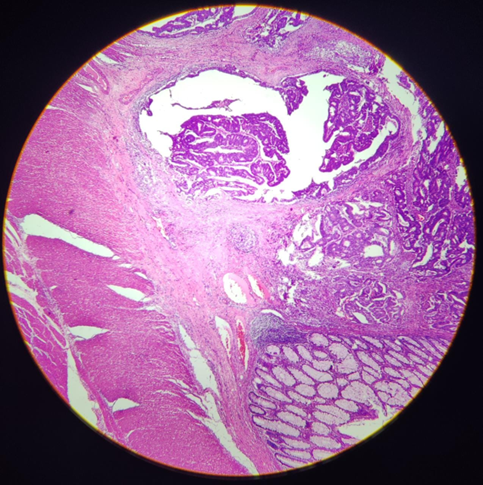

Órgão: Tuba Uterina.

Descrição: Corte histológico da tuba uterina que apresenta inflamação aguda caracterizada pela presença de exsudato neutrofílico na luz e na parede do órgão com áreas de necrose de liquefação. Presença de edema, hemorragia e fibrina.

Diagnóstico: Salpingite aguda (inflamação aguda).